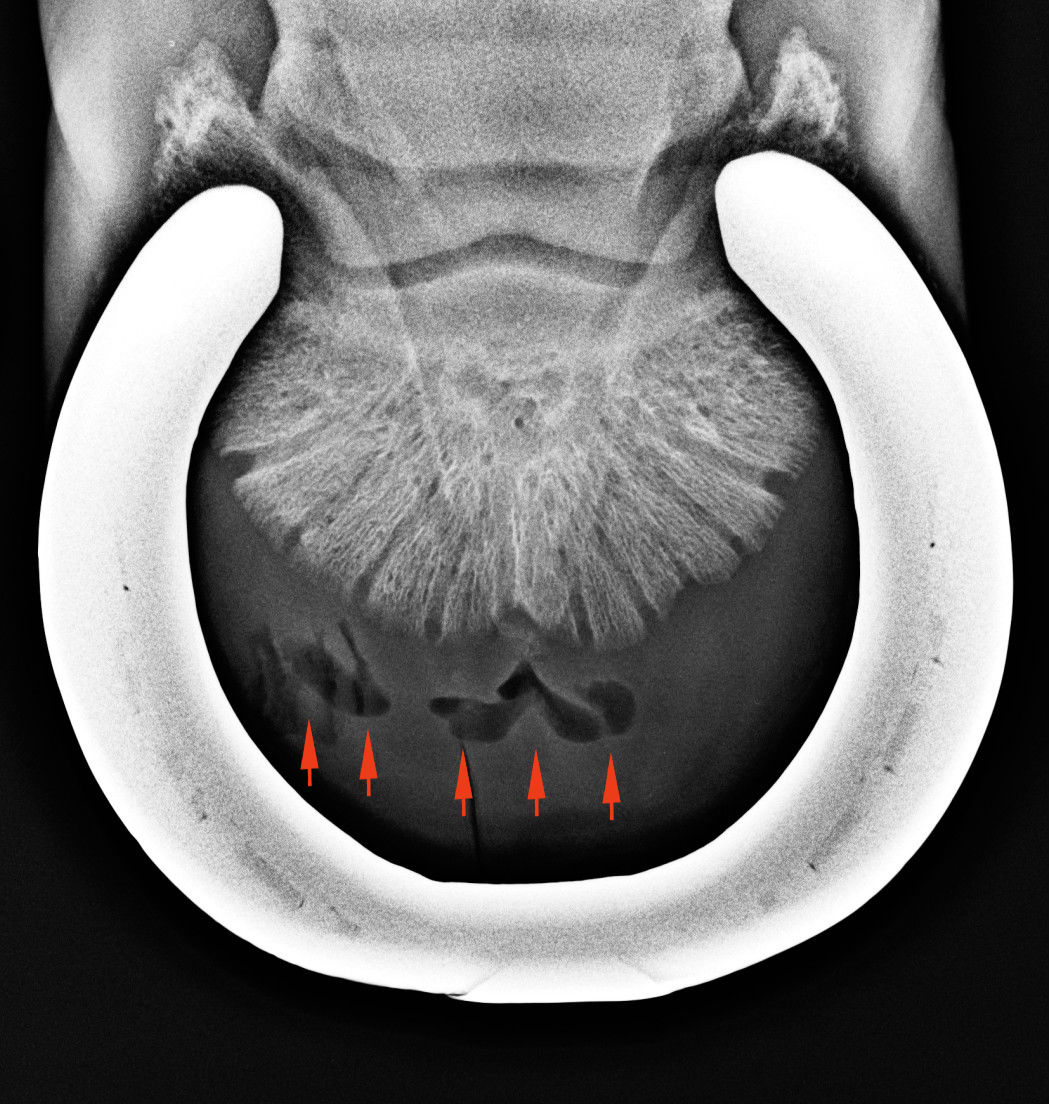

patatalyog oxspring

A piros nyilak a tályogban képződő gázbuborékokat mutatják.